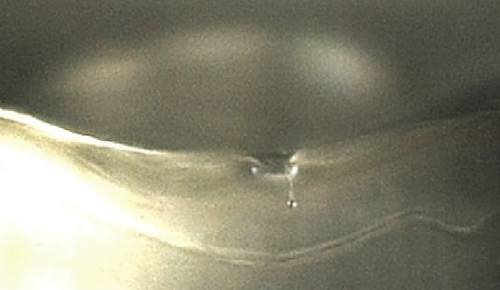

固体(アイス・ニードリング) VS 液体浸透比較

個体(アイス・ニードリング)

氷の粒子は衝突時に変形されずに表面を通り抜けます。これにより、薬剤を皮内へ浸透させることが可能です。

液体

液体は衝突時に変形されて表面から飛び跳ねます。よって、薬剤が液状で皮膚表面に残るようになります。

アイス・ニードリングは、表皮と真皮の境界にあたる表皮真皮接合部(DEJ)を正確にターゲットとしています。ターゲットクールを用いて希望の薬剤を導入することで、薬剤成分が表皮から真皮にかけて作用し、より効率的かつ素早い効果を実感いただけます。